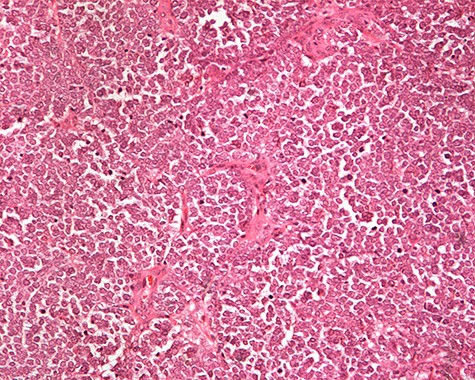

The patient was subsequently submitted to excision of the lesion on the right arm and lymph node dissection of the right axilla. Pathology examination of the mass revealed a primary MCC with neoplastic cells displaying round nuclei with scant cytoplasm, sites of necrosis, frequent mitoses and lymph cell infiltration (Fig. 1). Immunohistochemistry showed positive stain for CK20, chromogranin, NSE, EMA, and CD67, and negative stain for CD-57 and TTF-1 (Figs 2 and 3). Two out of fourteen 14 excised axillary lymph nodes were proven to be metastatic of this tumor.

Monotonous round cells with a scant cytoplasmic rim, round vesicular nuclei, apoptotic bodies and mitoses ×20 H&E.